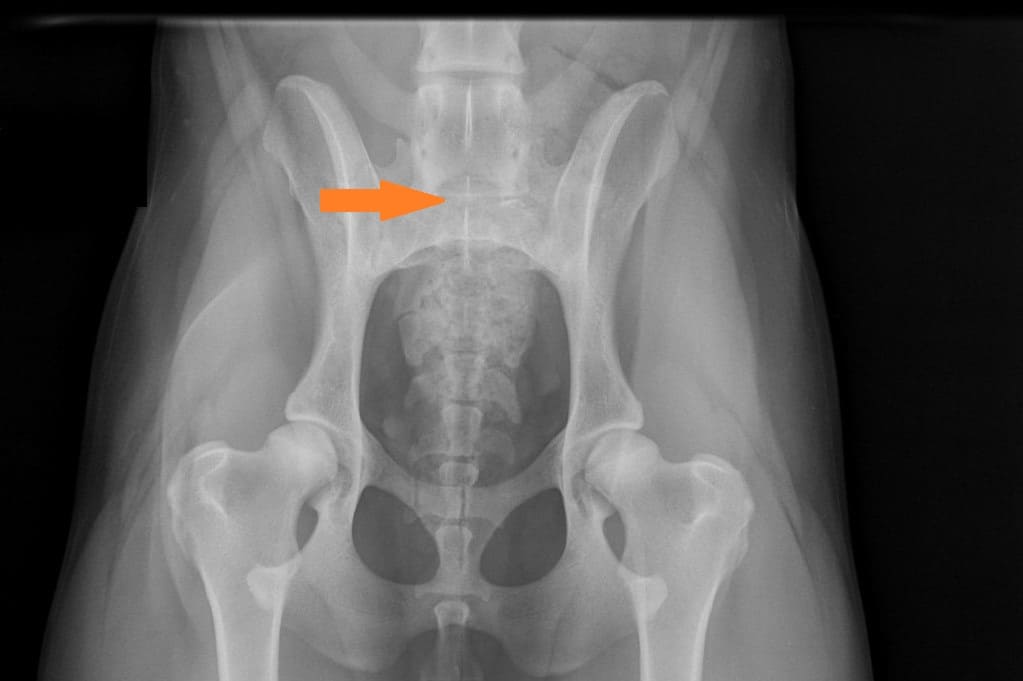

LTV3; asymmetrical; on the right in the VD photo the left side of S1 is shaped like a sacral vertebra and on the right side S1 is shaped like a lumbar vertebra including the spinous process.

The asymmetrical form, LTV3, seems to be a bit more tricky than the other forms. In some cases asymmetrical form comes with rotated pelvis, which might lead to unilateral development in hips. This is actually very logical; when the pelvis is not straight and in balance there will be uneven bear of weight between hips. In long term this uneven state might cause the worse hip wear sooner than the better hip and lameness and osteoarthritis may occur.

In the Finnish Kennel Club’s database 38,9% of Rhodesian Ridgebacks with LTV3 have one hip scored 1-2 degrees lower than the other one, ie. A/C (Oct 2020). The score doesn’t tell if the dog’s pelvis is straight or rotated.